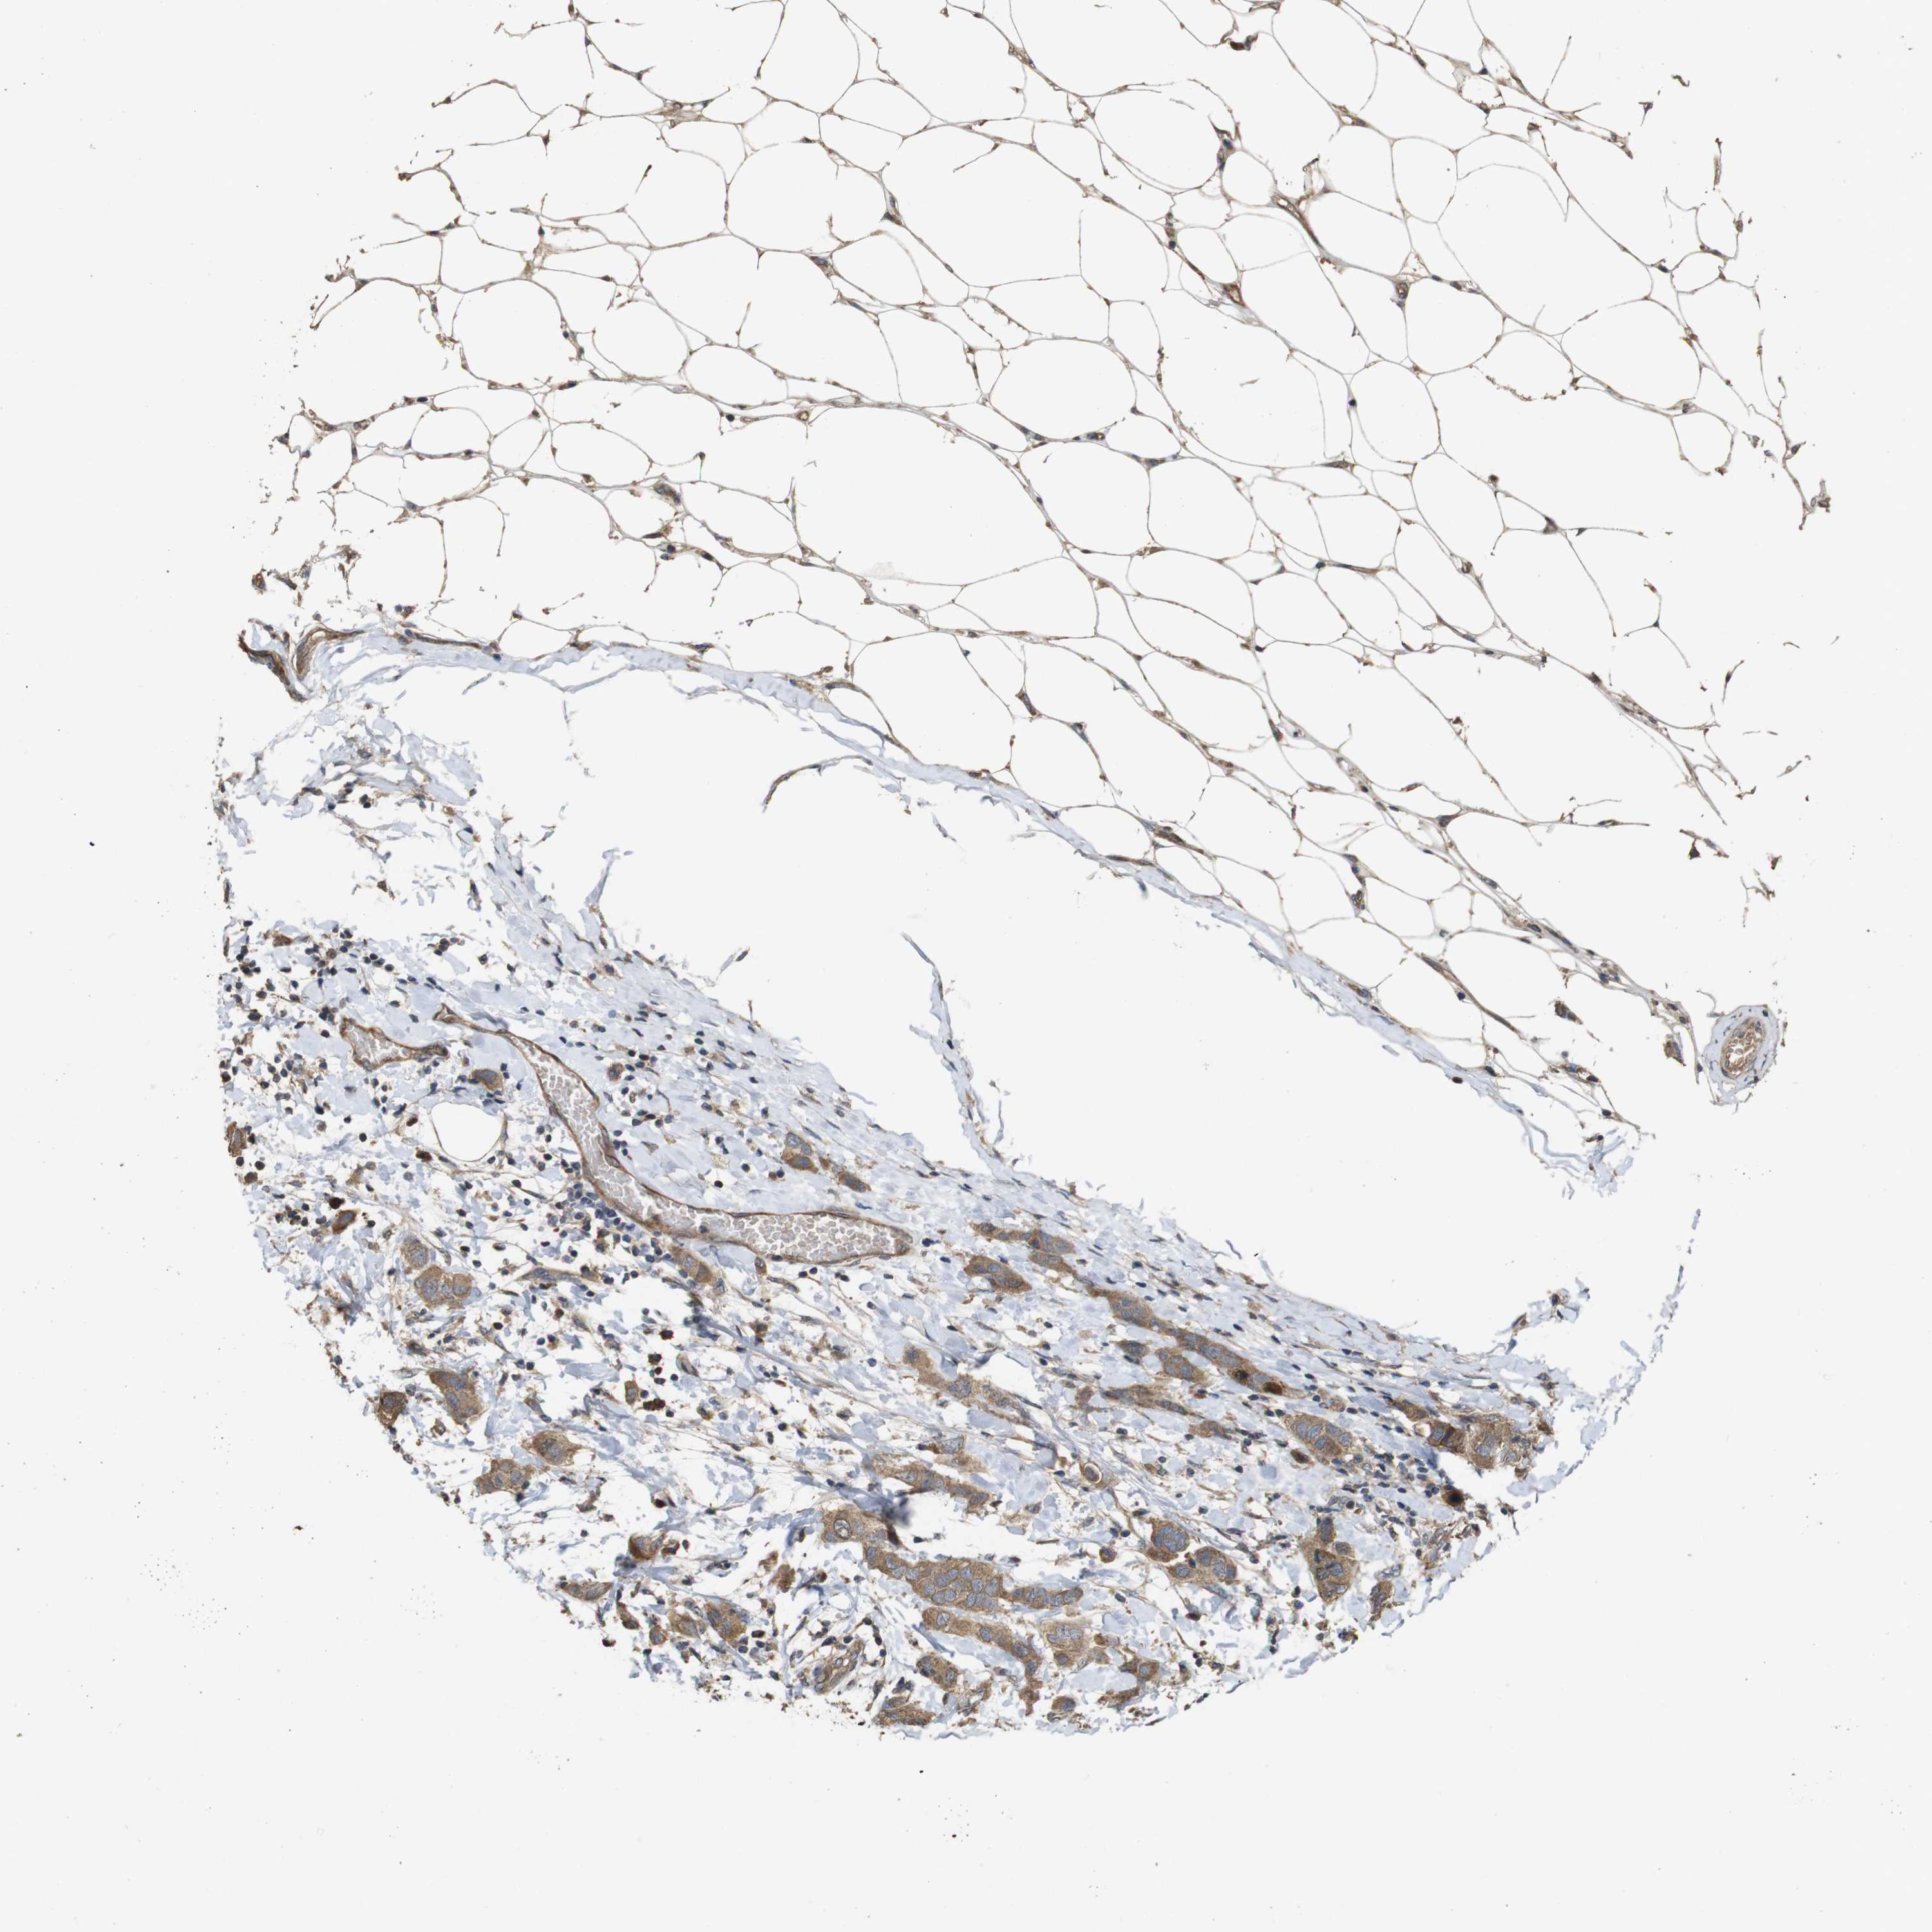

CANCER BREAST CANCER Show tissue menu

BRCA TCGA BRCA VALIDATION PROTEIN EXPRESSION